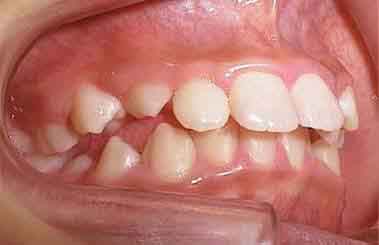

初診の状態